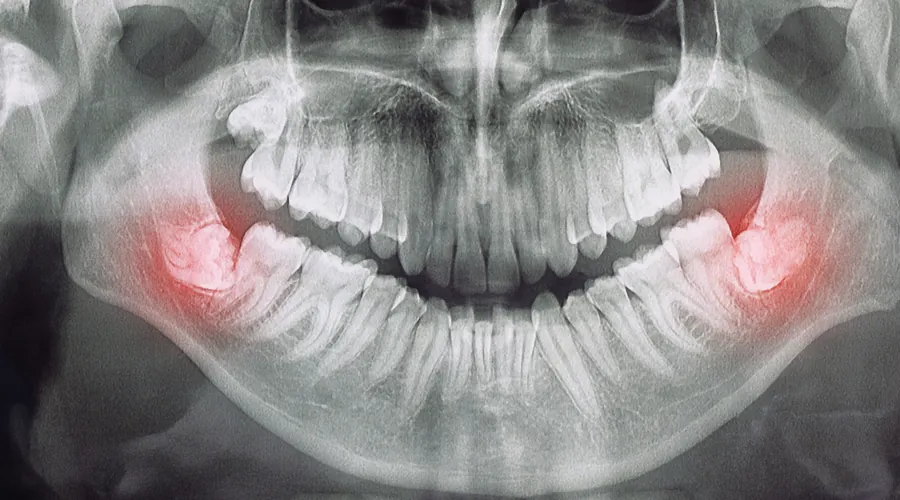

Dental implants can be used to treat missing teeth due to any reason like

Injury

Tooth decay

Infection

Sports

Impaction

Esthetics